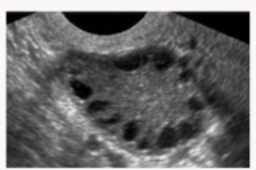

The “string of pearls sign”: a rounded ovary with multiple small immature follicles on the periphery is what condition?

PCOS